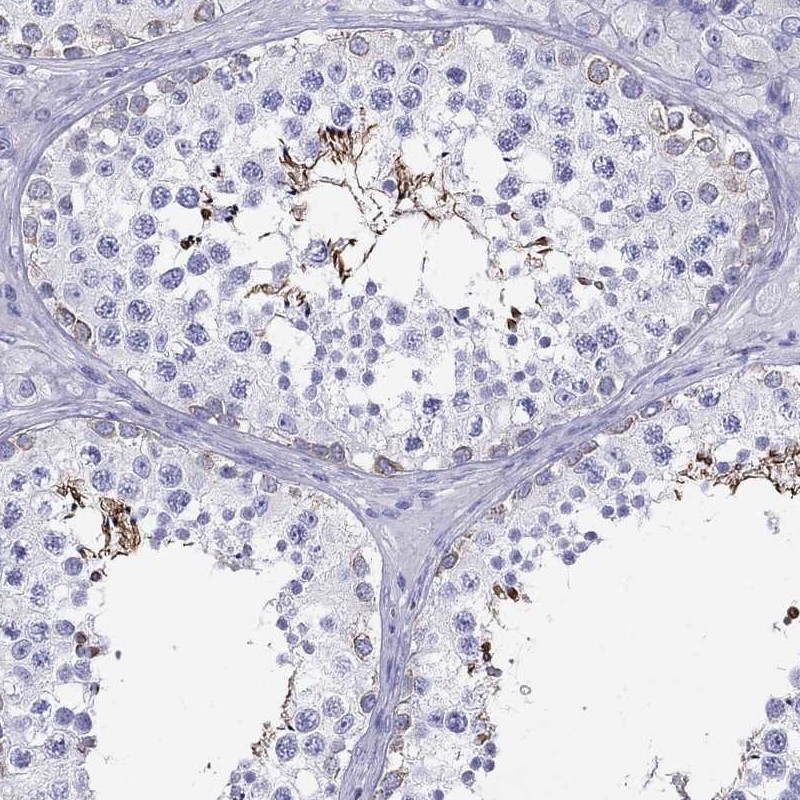

Immunohistochemical staining of human testis shows strong cytoplasmic positivity in cells in seminiferous ducts.